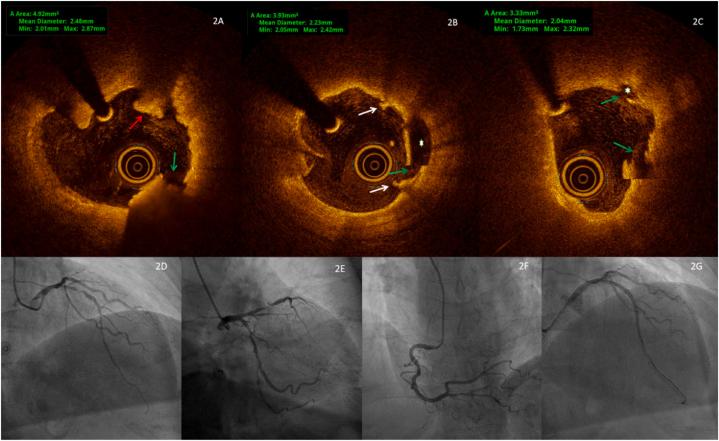

The de Winter electrocardiogram (ECG) pattern indicates severe stenosis or occlusion of the left anterior descending artery (LAD). We present a 72-year-old female with 1.5-h chest pain. Angiography and optical coherence tomography (OCT) revealed 90 % LAD stenosis with plaque rupture, but no ST-segment elevation in the precordial leads. The de Winter pattern, characterized by upsloping ST-segment depression in V1-V6, appeared only in lead V2. Following successful percutaneous coronary intervention (PCI), the de Winter pattern disappeared. This case underscores the significance of the de Winter pattern in one precordial lead, necessitating prompt angiography and PCI for improved patient outcomes.

德温特心电图(ECG)模式提示左前降支动脉(LAD)严重狭窄或闭塞。我们报告一名72岁女性,有1.5小时胸痛症状。血管造影和光学相干断层扫描(OCT)显示LAD狭窄90%伴斑块破裂,但胸前导联无ST段抬高。德温特模式表现为V1-V6导联ST段下斜型压低,仅在V2导联出现。成功进行经皮冠状动脉介入治疗(PCI)后,德温特模式消失。该病例强调了胸前导联出现德温特模式的重要性,需要及时进行血管造影和PCI以改善患者预后。